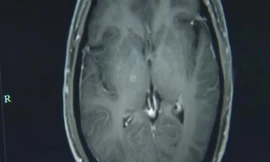

TPO - Một người đàn ông 43 tuổi ở Trung Quốc bị co giật và mất ý thức đã phải nhập viện sau khi các triệu chứng kéo dài trong vài tuần. Các bác sỹ phát hiện ra rằng trong não và ngực của anh ta có hàng trăm con sán dây đang cư trú.